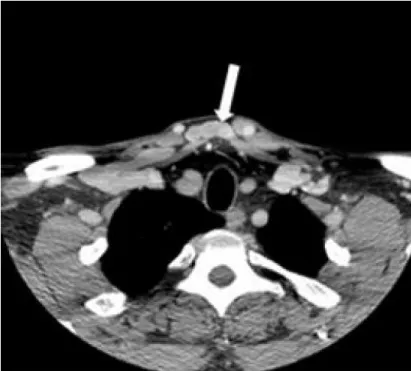

Clinical examination revealed a soft, compressible, painless mass on suprasternal space. The overlying skin was intact, and no lymphadenopathy was palpable. ENT and oral examination were normal. Clinical assessment clearly suggested a benign venous mass. A computed tomography angiography (CTA) of the head and neck was requested to expedite the diagnosis. The axial CTA of the root neck in the venous phase showed a median cervical swelling corresponding to a vein communicating between the two anterior jugular veins (Figure 2). The reconstruction in the coronal plane confimed an enlarged JVA (Figure 3).